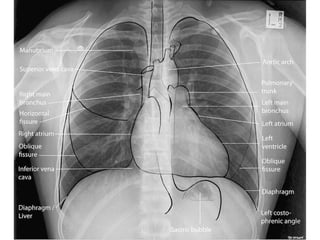

Este documento fornece parâmetros técnicos para realizar uma radiografia de tórax, incluindo posicionamento correto do paciente, dose adequada de radiação e estruturas anatômicas a serem avaliadas, como coração, pulmões, pleura, diafragma e ossos do tórax.